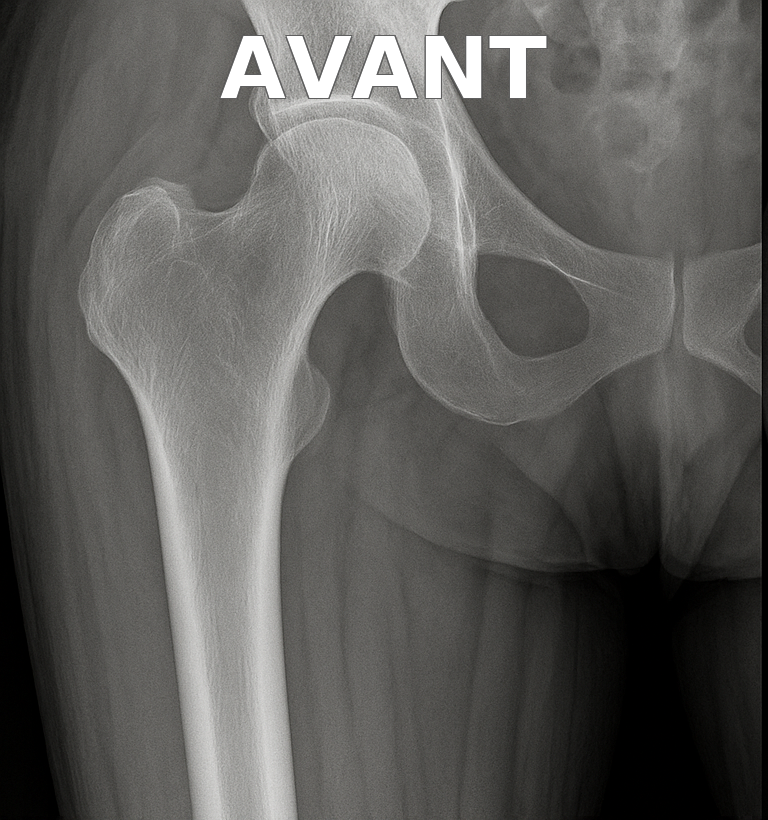

Illustration radiologique

Prothèse de hanche